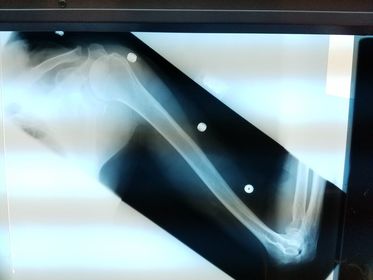

Which projection/position is this? PA Lateral Humerus

Projection/position? Lateral Humerus